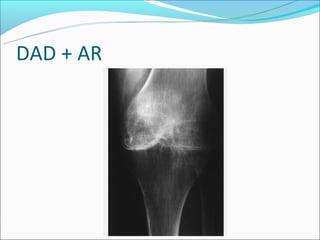

Cisto Subcondral ou Geodo

Formações císticas ao

redor das articulações

em vários distúrbios

como DAD e AR e

necrose avascular.

DAD + AR